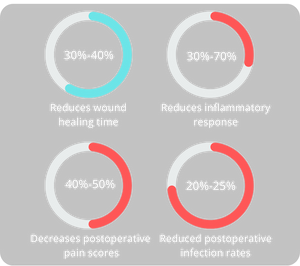

Red light lowers pro-inflammatory cytokines like TNF-α and boosts antioxidant defenses, reducing oxidative damage. It effectively alleviates arthritis pain, post-surgical swelling, and skin inflammation, such as acne and eczema.

Scientific Support: Nature Reviews Immunology noted red light shifts cells from inflammation to repair. In rheumatoid arthritis studies, it reduced pain by 55% and reliance on medication.

Red light speeds up wound closure by promoting fibroblast activity, collagen synthesis, and blood flow. It is effective for diabetic ulcers, surgical scars, and burns, while also aiding cosmetic recovery.

Scientific Support: A 2021 study in Wound Repair and Regeneration found red light improved diabetic ulcer healing by 60%, reducing infection risks.